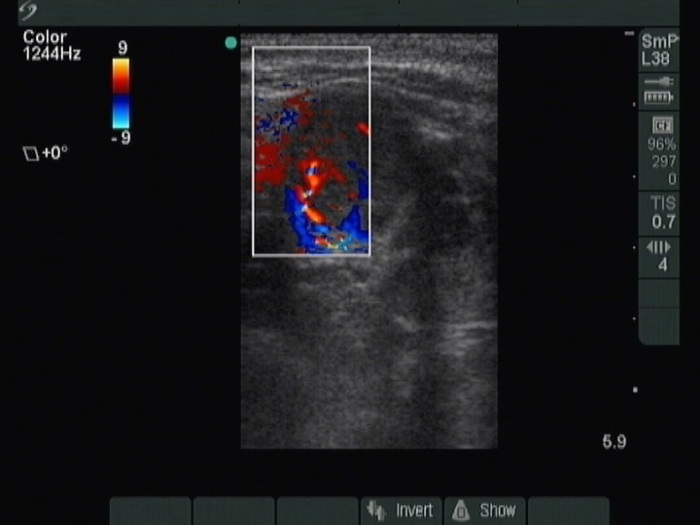

Thyroid cancers - case 1219 (ultrasonographic picture 5)

Lower third of the right lobe, transverse scan, color Doppler mode. Th nodule shows both perinodular and intranodular vascularity.